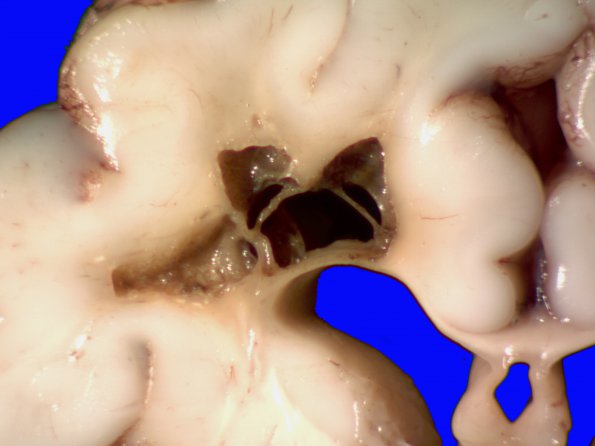

10C2 H-I, HLH, neonatal 34wk & 6wk (Case 10) A_5

Higher magnification of image #10C1.